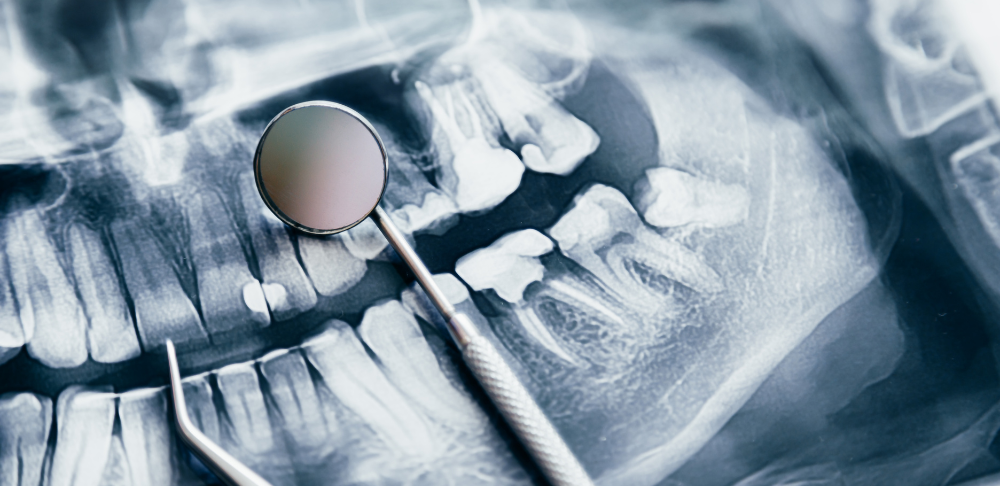

RTG zębów to jedno z najczęściej wykonywanych badań diagnostycznych w stomatologii. Dzięki nowoczesnej technologii pozwala na precyzyjne zobrazowanie uzębienia, tkanek miękkich oraz kości szczęki. Jeśli czeka Cię wykonanie prześwietlenia, pewnie zastanawiasz się, jak się do niego przygotować i co warto wiedzieć. Zdjęcie rentgenowskie wykorzystuje promieniowanie do zobrazowania struktur niewidocznych gołym okiem. Stomatolog może dzięki niemu ocenić stan zdrowia zębów, korzeni, kości szczęki oraz stawów skroniowo-żuchwowych. RTG zębów jest niezbędne w diagnostyce próchnicy głębokiej i ukrytej, ocenie stanu korzeni oraz planowaniu leczenia kanałowego, implantologicznego czy ortodontycznego. Jest również konieczne w przypadku podejrzeń zmian zapalnych, urazów czy nieprawidłowości rozwojowych.

W zależności od potrzeb diagnostycznych wykonuje się kilka rodzajów RTG zębów. Zdjęcie punktowe obejmuje jeden lub kilka zębów i jest podstawowym badaniem przy próchnicy czy leczeniu kanałowym. Zdjęcie panoramiczne, czyli pantomogram, pozwala zobaczyć wszystkie zęby, kości szczęki i stawy, co jest niezbędne w ortodoncji czy chirurgii stomatologicznej. Tomografia komputerowa CBCT tworzy trójwymiarowy obraz struktur twarzoczaszki, co sprawdza się w zaawansowanych przypadkach chirurgicznych i implantologicznych. Zdjęcie cefalometryczne stosowane jest głównie w ortodoncji do oceny relacji między zębami a kośćmi i tkankami miękkimi.

Regularne wykonywanie RTG zębów ma ogromne znaczenie dla zdrowia jamy ustnej. Pozwala na wczesne wykrycie problemów, które nie dają widocznych objawów, takich jak próchnica, zmiany zapalne czy choroby przyzębia. Dzięki temu można podjąć leczenie na wczesnym etapie, co zwiększa jego skuteczność, skraca czas trwania terapii i minimalizuje jej koszty. RTG zębów jest również niezbędne do monitorowania postępów leczenia ortodontycznego czy po zabiegach chirurgicznych.